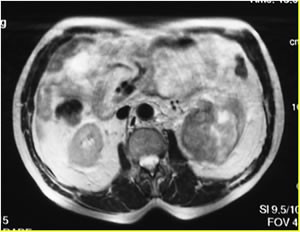

МРТ

забрюшинного пространства

Опухолевый узел левой почки

Mts в правый надпочечник

Основной: ПКР слева Т3 Nx

M1.